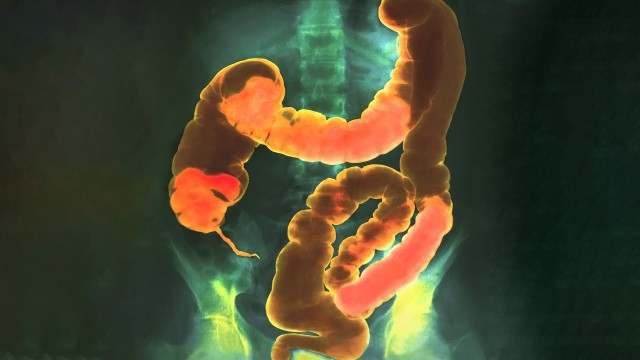

• S2021E04 A Student Drank 2 Liters Fiber Supplement For Dinner. This Is What Happened To His Intestines.

This may or may not have been from personal experience. Please don't make your psyllium husk fiber into jelly. Very painful